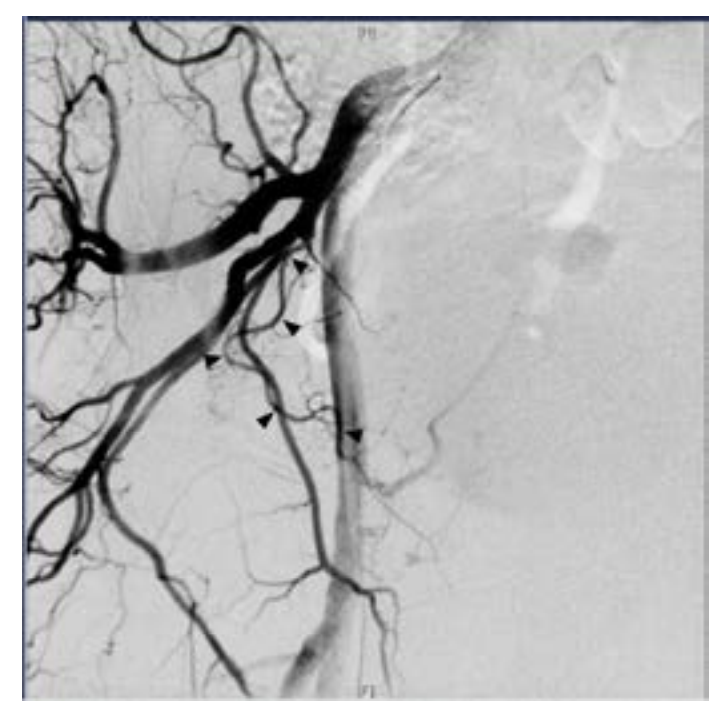

A 74-year-old male with past medical history of hypertension, coronary artery disease, and BPH with LUTS refractory to medical management presented for evaluation. The patient underwent an MRI of the prostate demonstrating a 182 cc gland with an enlarged transitional zone measuring 144 cc (Figure 1). The patient’s baseline IPSS and QoL were 18 and 5, respectively. Given the patient’s prostate gland size, and medical comorbidities, he elected to undergo PAE for management of his LUTS. On the day of his PAE, right common femoral arterial access was obtained and a pigtail DSA was obtained delineating pelvic arterial anatomy. On the right, the prostatic artery arose from a vesiculoprostatic trunk, with a shared origin with the superior vesicular artery (Figure 2). This was selectively catheterized with a progreat alpha microcatheter (Terumo, Tokyo, Japan), and 016” fathom microwire (Boston Scientific, Marlborough, MA). Angiography demonstrated perfusion of the entire right portion of the gland, without evidence of extra-prostatic supply (Figure 3). Embolization was performed with 300-500 micron Embospheres (Merit Medical, South Jordan, UT) to stasis. On the left, the prostatic artery arose from the left obturator artery (Figure 4). This was subsequently catheterized with the same catheter/wire combination, with angiography demonstrating left glandular perfusion without extra-prostatic supply (Figure 5). Embolization was again performed to stasis with 300-500 micron Embospheres. The patient did well post-procedurally with self-limited urinary frequency and dysuria for 3 days. By 3 months post PAE, the patient reported a significant improvement in his LUTS, with an IPSS/QoL of 3 and 0, respectively.

Initial arterial access was obtained and a pigtail catheter was advanced into the abdominal aorta to the level of the aortic bifurcation. Using a hybrid angio-CT unit (Nexaris, Siemens Healthcare AG, Forchheim, Germany), a CTA was obtained to delineate arterial anatomy and determine the pattern of glandular reperfusion. Multiplanar reconstruction was performed using syngo DynaCT and Embolization Guidance software (Siemens Healthcare AG, Forchheim, Germany). These images demonstrated no perfusion from either the previously treated right or left prostatic arteries, which now appeared markedly attenuated. Instead, the majority of the gland had been revascularized through a distal internal pudendal artery collateral on the right, with more proximal branches perfusing the cavernosal tissues (Figure 7). These cavernosal branches also appeared to be the sole supply to the cavernosal tissues on the right, and therefore critical to avoid nontarget embolization to penile tissues. The CTA/Embolization Guidance data sets were then fused to create an overlay of the vessel trajectory to be displayed during 2D fluoroscopy. Given the vessel tortuosity and small caliber size (Figure 8), an Excelsior SL-10 microcatheter (Stryker, Fremont, CA) and 014’ Synchrosoft microwire (Stryker) were used to select the terminal branch of the internal pudendal artery distal to the cavernosal branches. Angiography from this location demonstrated brisk antegrade flow with perfusion of the central gland without extra-prostatic perfusion (Figure 9). Embolization was performed to stasis using 300-500 micron particles. Completion angiography demonstrated no further prostatic perfusion and preservation of more proximal cavernosal branches. The patient had an uneventful postoperative course, and by 1 month post PAE his IPSS/QoL was 3/0, respectively.